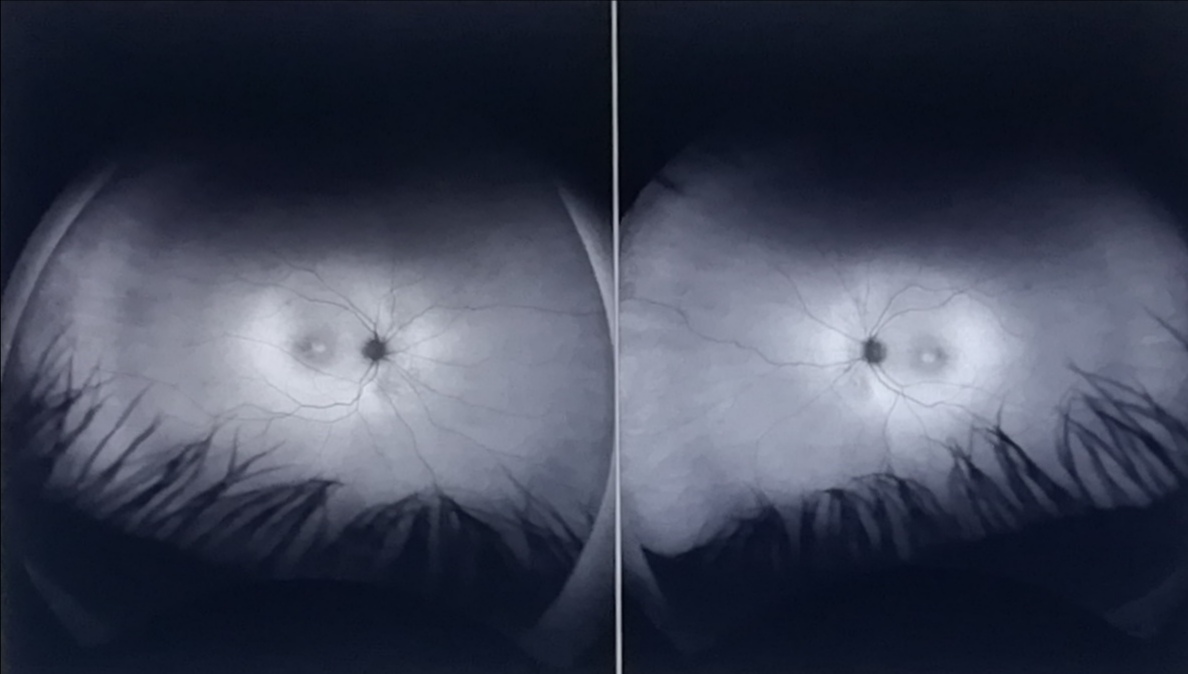

Every eighteen months or so, I attend an eye-monitoring appointment at NHS Moorfields situated not far from the ‘Old Street’ Tube Stop on the Northern Line (Via Bank). Although subsequent Tory, LibDems and Labour governments have conspired to ‘shut-down’ and ‘privatise’ the Socialist ‘National Health Service’ – a core of staff working under third-world conditions (due to the British Tory government starving the institution of finance, resources and technology) – strive to provide a ‘free at the point of use’ service! Indeed, the British taxpayer already funds the NHS many times over and the current crisis of a lack of resources is entirely fabricated and intended to drive a frightened and desperate populace into taking-out ‘private health’. We refuse to do this and continue to make use of the Socialist NHS that is left! What follows is a photographic journey to and from Moorfields – one of the best eye hospitals in the world!